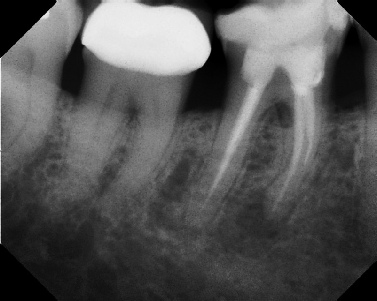

COMPLICATED ANATOMY LARGE LESIONS CALCIFIED CANALS PERFORATION / RESORPTION SEPARATED INSTRUMENTS SURGICAL CASES RETREATMENT / pOST REMOVAL OPEN APICES ACCESS THRU CROWNS Root Canal Case Portfolio

Pre-op Post-op 1 Post-op 2